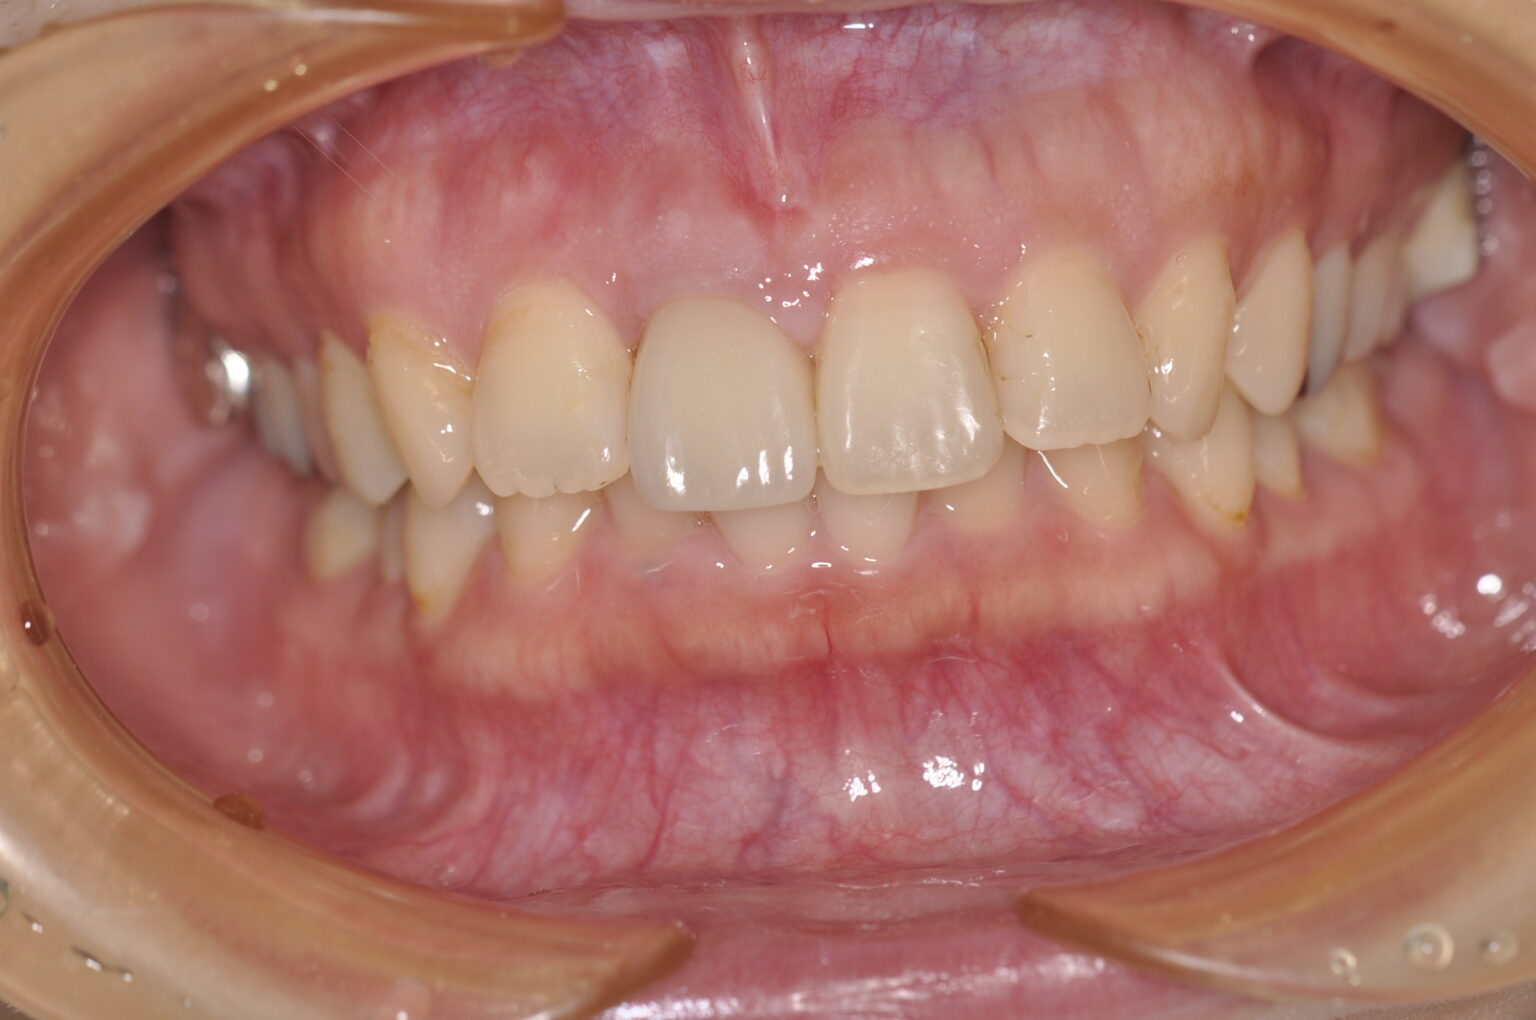

BEFORE症例写真

AFTER症例写真